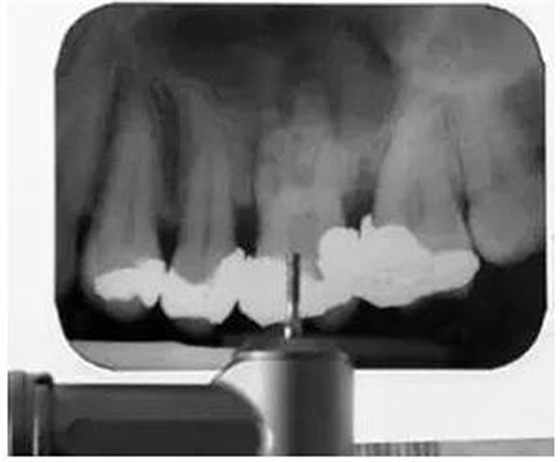

為了確保實(shí)現(xiàn)滿意的治療效果,在治療中要不斷確認(rèn)工作長(zhǎng)度和充填質(zhì)量。在備樁或者進(jìn)行鈣化根管的根管治療時(shí),要拍攝根尖X線片以確保鉆或根管銼的方向是正確的(圖4)。這可以有效地防止治療失誤,如不必要的髓室底或者側(cè)壁穿孔。